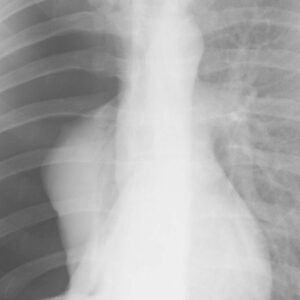

Pneumothorax is also called a collapsed lung. When air enters the pleural cavity (the space between the lung and chest wall), the buildup of air puts pressure on the lung. The pressure decreases the lung’s ability to expand and recoil with inspiration and expiration, resulting in lung collapse. The development of pneumothorax can be life-threatening and may require rapid interventions. This course will discuss traumatic and atraumatic pneumothorax, their signs and symptoms, treatment methods, and chest tube management.